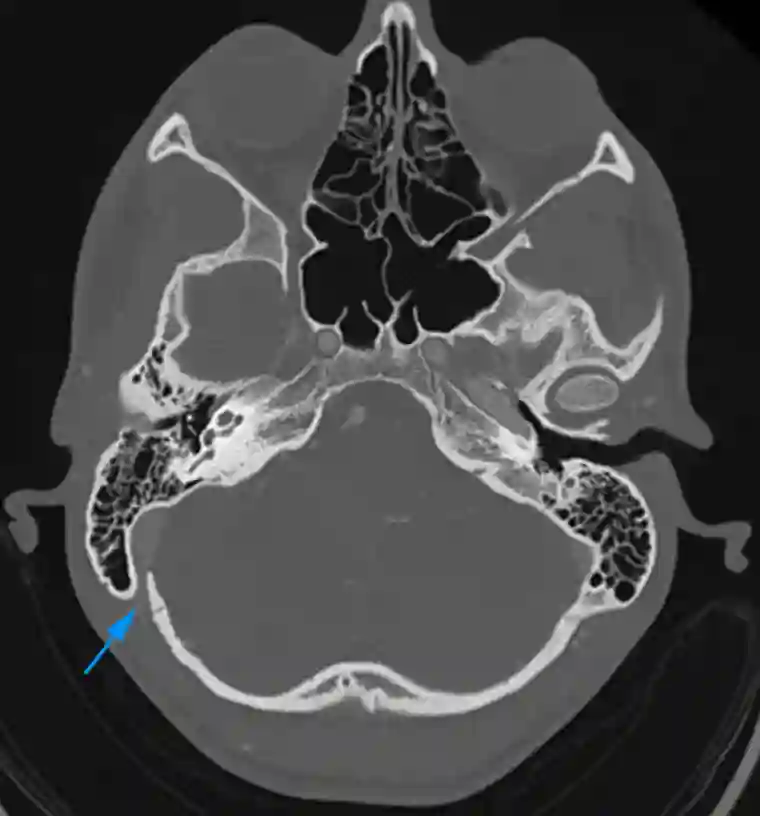

Foramen mastoideum im CT

Axiales CT Bild mit Darstellung des Foramen mastoideum (blauer Pfeil).